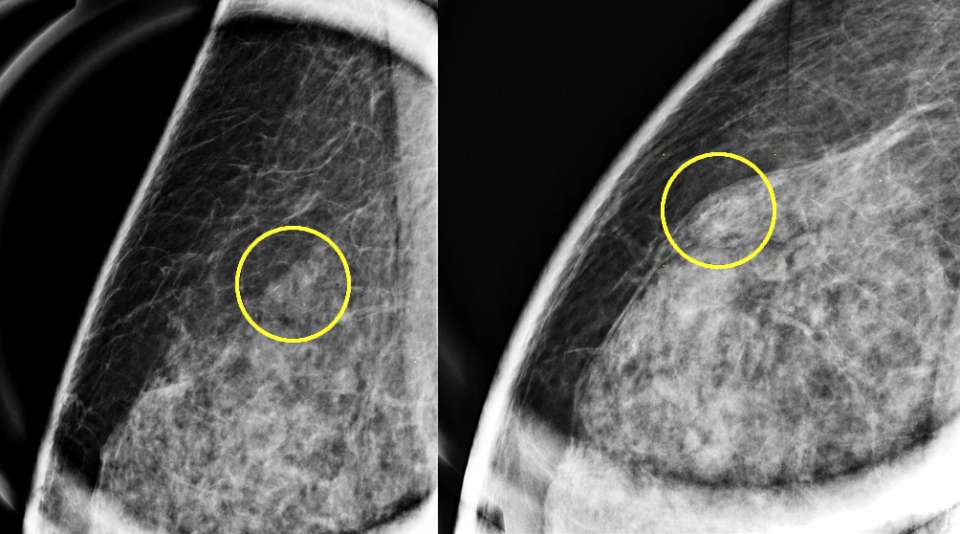

Imaging Appearance

The imaging appearance of FEA, as with other columnar cell changes, is non-specific. The most common presentation is grouped, amorphous calcifications on mammography.1,2 Likewise, the ultrasound appearance is non-specific, but it most often presents as irregular mass.2 The MRI appearance of FEA is not well-established and is also likely non-specific.1,2